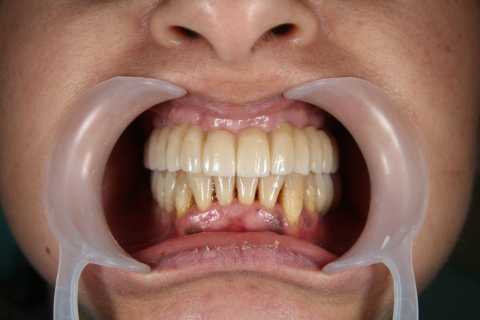

Implanturi mandibulă și lucrare înșurabilă ceramică

Cazul 66: Implant dentar MegaGen AnyRidge

Pacient în vârstă de 77 de ani, purtător de proteză mobilă de peste 20 de ani, nemulțumit de faptul că nu mai poate purta proteza din cauza rezorbției osoase la nivelul mandibulei, se hotărăște pentru o reabilitare protetică fixă cu ajutorul implanturilor dentare și a unei lucrări înșurubabile din ceramică pe suport de titan.